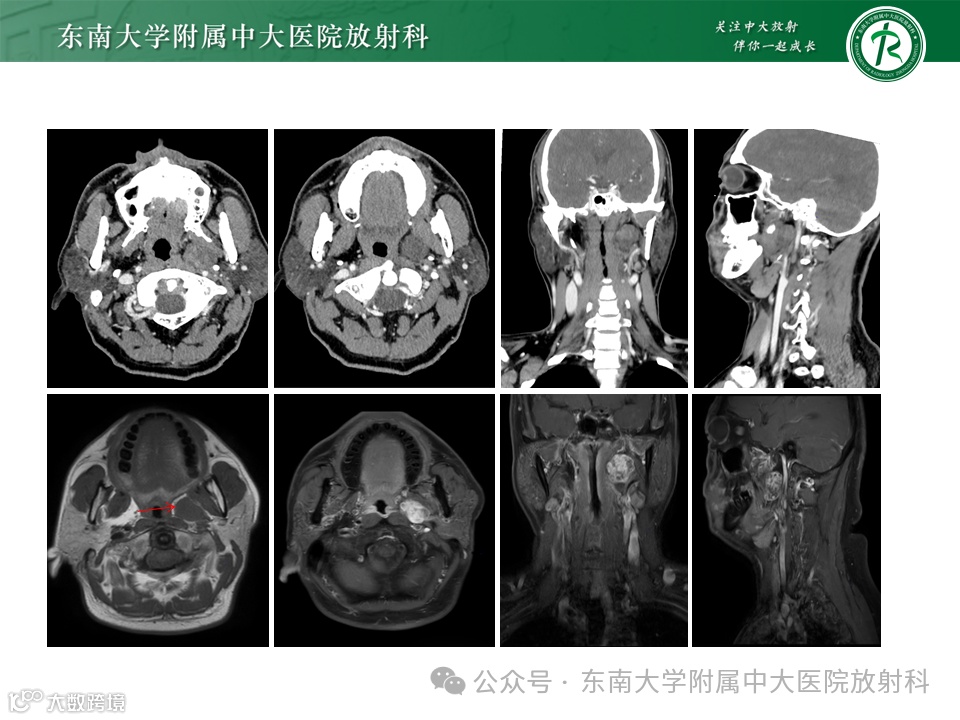

患者,女,38岁

主诉:咽部异物40余天

影像学表现